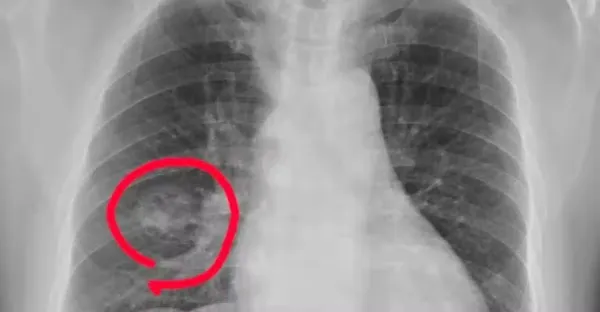

手腳出現 4 種異常,可能是得肺癌了,千萬不要大意